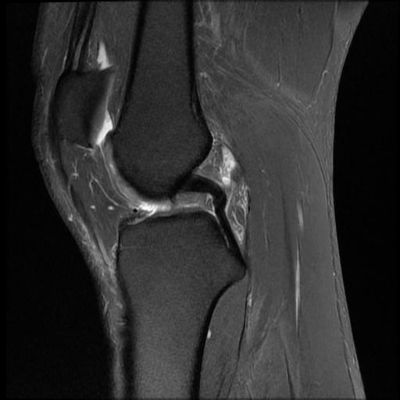

图1展示了MBSMFFPN模型在股骨MRI图像上的检测结果。从图中可以看出,模型能够准确识别和定位股骨的各个关键结构,包括骨髓腔、皮质骨和周围软组织。特别值得注意的是,对于边界模糊的小目标(如早期骨髓腔病变),MBSMFFPN模型表现出色,这得益于多尺度特征融合机制和改进的检测头设计。